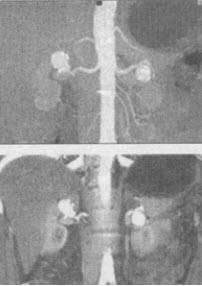

男,32岁,偶然发现有高血压,结合所示图像,最可能的诊断是()。

A、双侧肾动脉瘤

B、双侧假性肾动脉瘤

C、双侧肾动脉出血血肿形成

D、双侧肾动脉狭窄

E、双侧肾动脉夹层动脉瘤

A